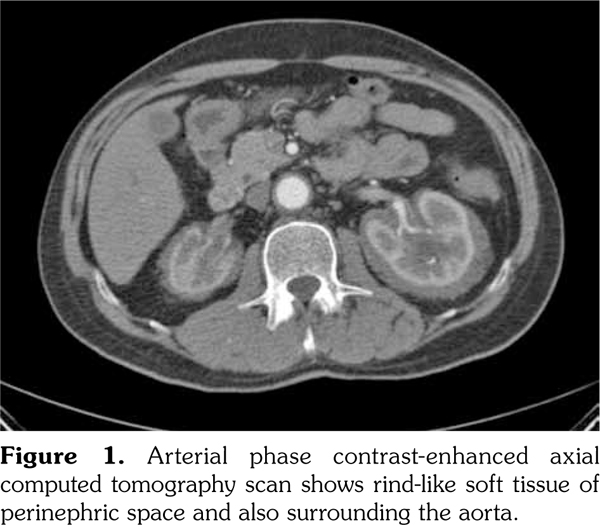

A 51-year-old male patient admitted to our outpatient clinic with complaints of flank pain and fatigue. He had a history of renal stones and peripheral arterial disease. He had a medically unmanageable hypertension. Blood pressure was 200/110 mmHg. Serum creatinine level was 1.2 mg/dL. He was evaluated with contrast- enhanced multislice computed tomography. Along with small calyceal stones, there was bilateral, quite symmetrical perinephric ''rind-like'' soft tissue infiltration. Right kidney was atrophic but still functioning without pelvicalyceal contrast excretion. The soft tissue infiltration obliterated both renal hila and caused proximal ureteral stenoses with mild calyceal dilation on the left side (Figures 1 and 2). Distally, the ureters were normal. Incidentally, abdominal aorta, common iliac arteries, proximal celiac trunk, and proximal renal arteries were noticed to appear “coated” with subtle perivascular tissue infiltration. An endovascular aortoiliac stent-graft was in place. He rejected any further diagnostic intervention after he presented with a blood creatinine of 2.2 mg/dL. He underwent an unenhanced computed tomography examination with the same findings before. Renal scintigraphy revealed a non-functioning right kidney. Perinephric soft tissue infiltration was considered as the differential diagnosis of ECD. Direct radiographies of the extremities were obtained. All of the long tubular bones showed diametaphyseal cortical and patchy medullary sclerosis reinforcing the diagnosis of ECD (Figure 3). The patient underwent right nephrectomy for the control of hypertension and a double-J stent was placed on the left side for the relief of ureteral obstruction. The nephrectomy specimen showed the typical histological features of ECD. Serum creatinine level dropped to the borderline values after the operation and his blood pressure was in the normal range with medications. The pathological analysis of the nephrectomy specimen revealed an inflammatory infiltrate formed by foamy histiocytes that were positively stained for CD68 and neutrophilic aggregates which confirmed the preoperative diagnosis (Figures 4 and 5). A written informed consent was obtained from the patient.

The histiocytic infiltrative process, as found in our case, may involve the retroperitoneum in approximately 29 to 68% of patients.(4,5) The soft tissue infiltrate around the aorta and its major branches can be misdiagnosed as arteritis, lymphoma or retroperitoneal fibrosis.(4) The process may lead to severe arterial stenosis and the consequences include cerebral ischemia, cardiac angina, mesenteric ischemia, or renovascular hypertension.(6-8) Adrenal glands, kidneys, renal arteries, ureters, and adjacent anatomical spaces may be involved in the process. Infiltration of perirenal space may extend to the pararenal space with irregular borders, thus will be given the name “hairy kidney”.(6) Extension to the renal sinuses and pedicles, proximal and distal ureters is possible and may cause obstruction and eventually, as in our case, compromise renal function.(8-10)

In our case, computed tomography findings suggested retroperitoneal fibrosis but the infiltrate did not involve the vena cava and the paraaortic infiltration was circumferential instead of sparing the posterior aspect of the aorta. Also, the perinephric infiltration was far more striking than the perivascular space which is inconsistent with retroperitoneal fibrosis. Therefore, the differential diagnosis consisted mainly of processes involving perinephric and perivascular spaces, namely, lymphoma, retroperitoneal fibrosis, and ECD. The diagnosis of ECD was strongly suggested with the radiographic findings of the extremities which revealed symmetrical dia-metaphyseal osteosclerosis.